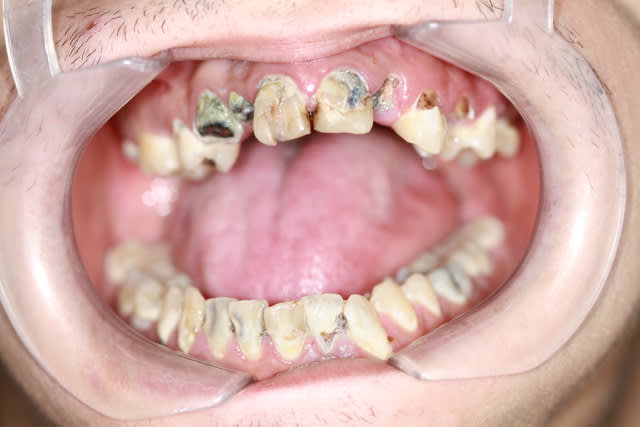

chicot29

Modeste contribution, rebasage au tartre.... Mais on peut faire mieux je n'ai pas détecté de vers à l'intérieur !